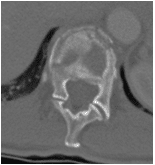

48 yo Female had a sledding injury when she landed on her buttocks following a fall. She felt a “pop” and immediate back pain. She was able to walk briefly, but quickly incapacitated by pain. Her examination suggested an injury to the lower thoracic spine. She was neurologically intact. She had uncontrolled pain. X Rays and CT scan of the patient showed fracture of T12 vertebral body.

The fracture was stabilized by Minimal Invasive spine surgery with percutaneous pedicle screws in T11, 12 and L1 and rod fixation.